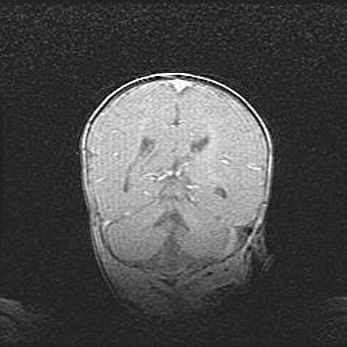

Мальформация Денди-Уокера. Киста задней черепной ямки.

Агенезия мозолистого тела.

Возраст: 2,5 месяца

Вес: 2420 г

Пол: женский

Окружность головы: 37 см

Срок гестации: 32 недели

Мальформация Денди—Уокера — редкий вид патологии ЦНС, представляющий собой врожденный порок развития каудального отдела ствола и червя мозжечка, ведущий к неполному раскрытию срединной (Мажанди) и латеральных (Лушка) апертур IV желудочка мозга. Для этогно синдрома характерна триада симптомов: гипотрофия червя мозжечка и/или полушарий мозжечка, кисты задней черепной ямки, гидроцефалия различной степени. В 70% случаев порок сочетается и с другими аномалиями головного мозга, в частности с агенезией мозолистого тела.